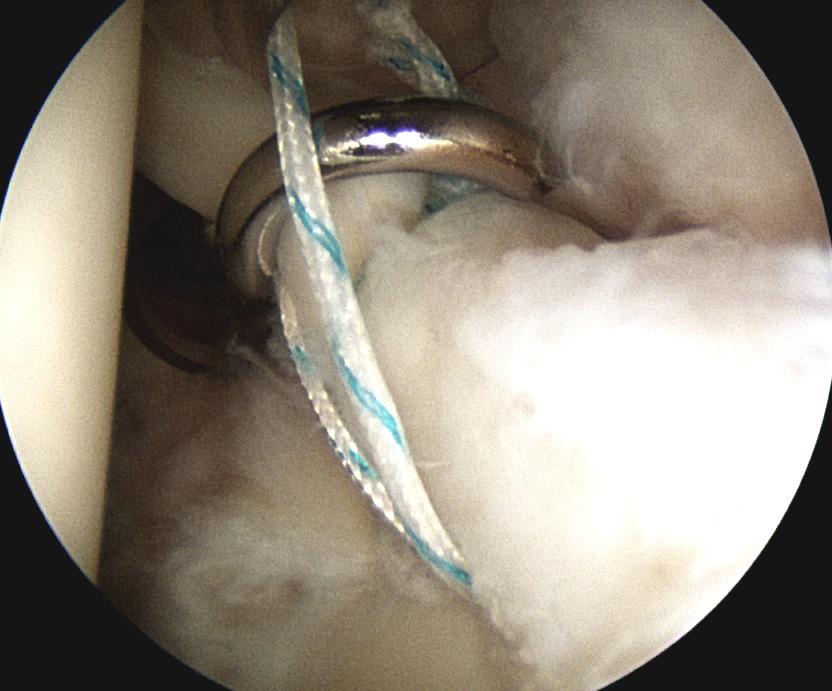

3. Anchors

Drill and insert via Wilminton portal

Technique

- insert anchor

- suture through each cannula

- limb through W portal will be the suture limb that is passed

- suture passer through anterior portal (right angled for left shoulder)

Anterior anchor

- best to pass the suture passer above the biceps to get good bite

- retrieve sutures and tie from port of Wilmington